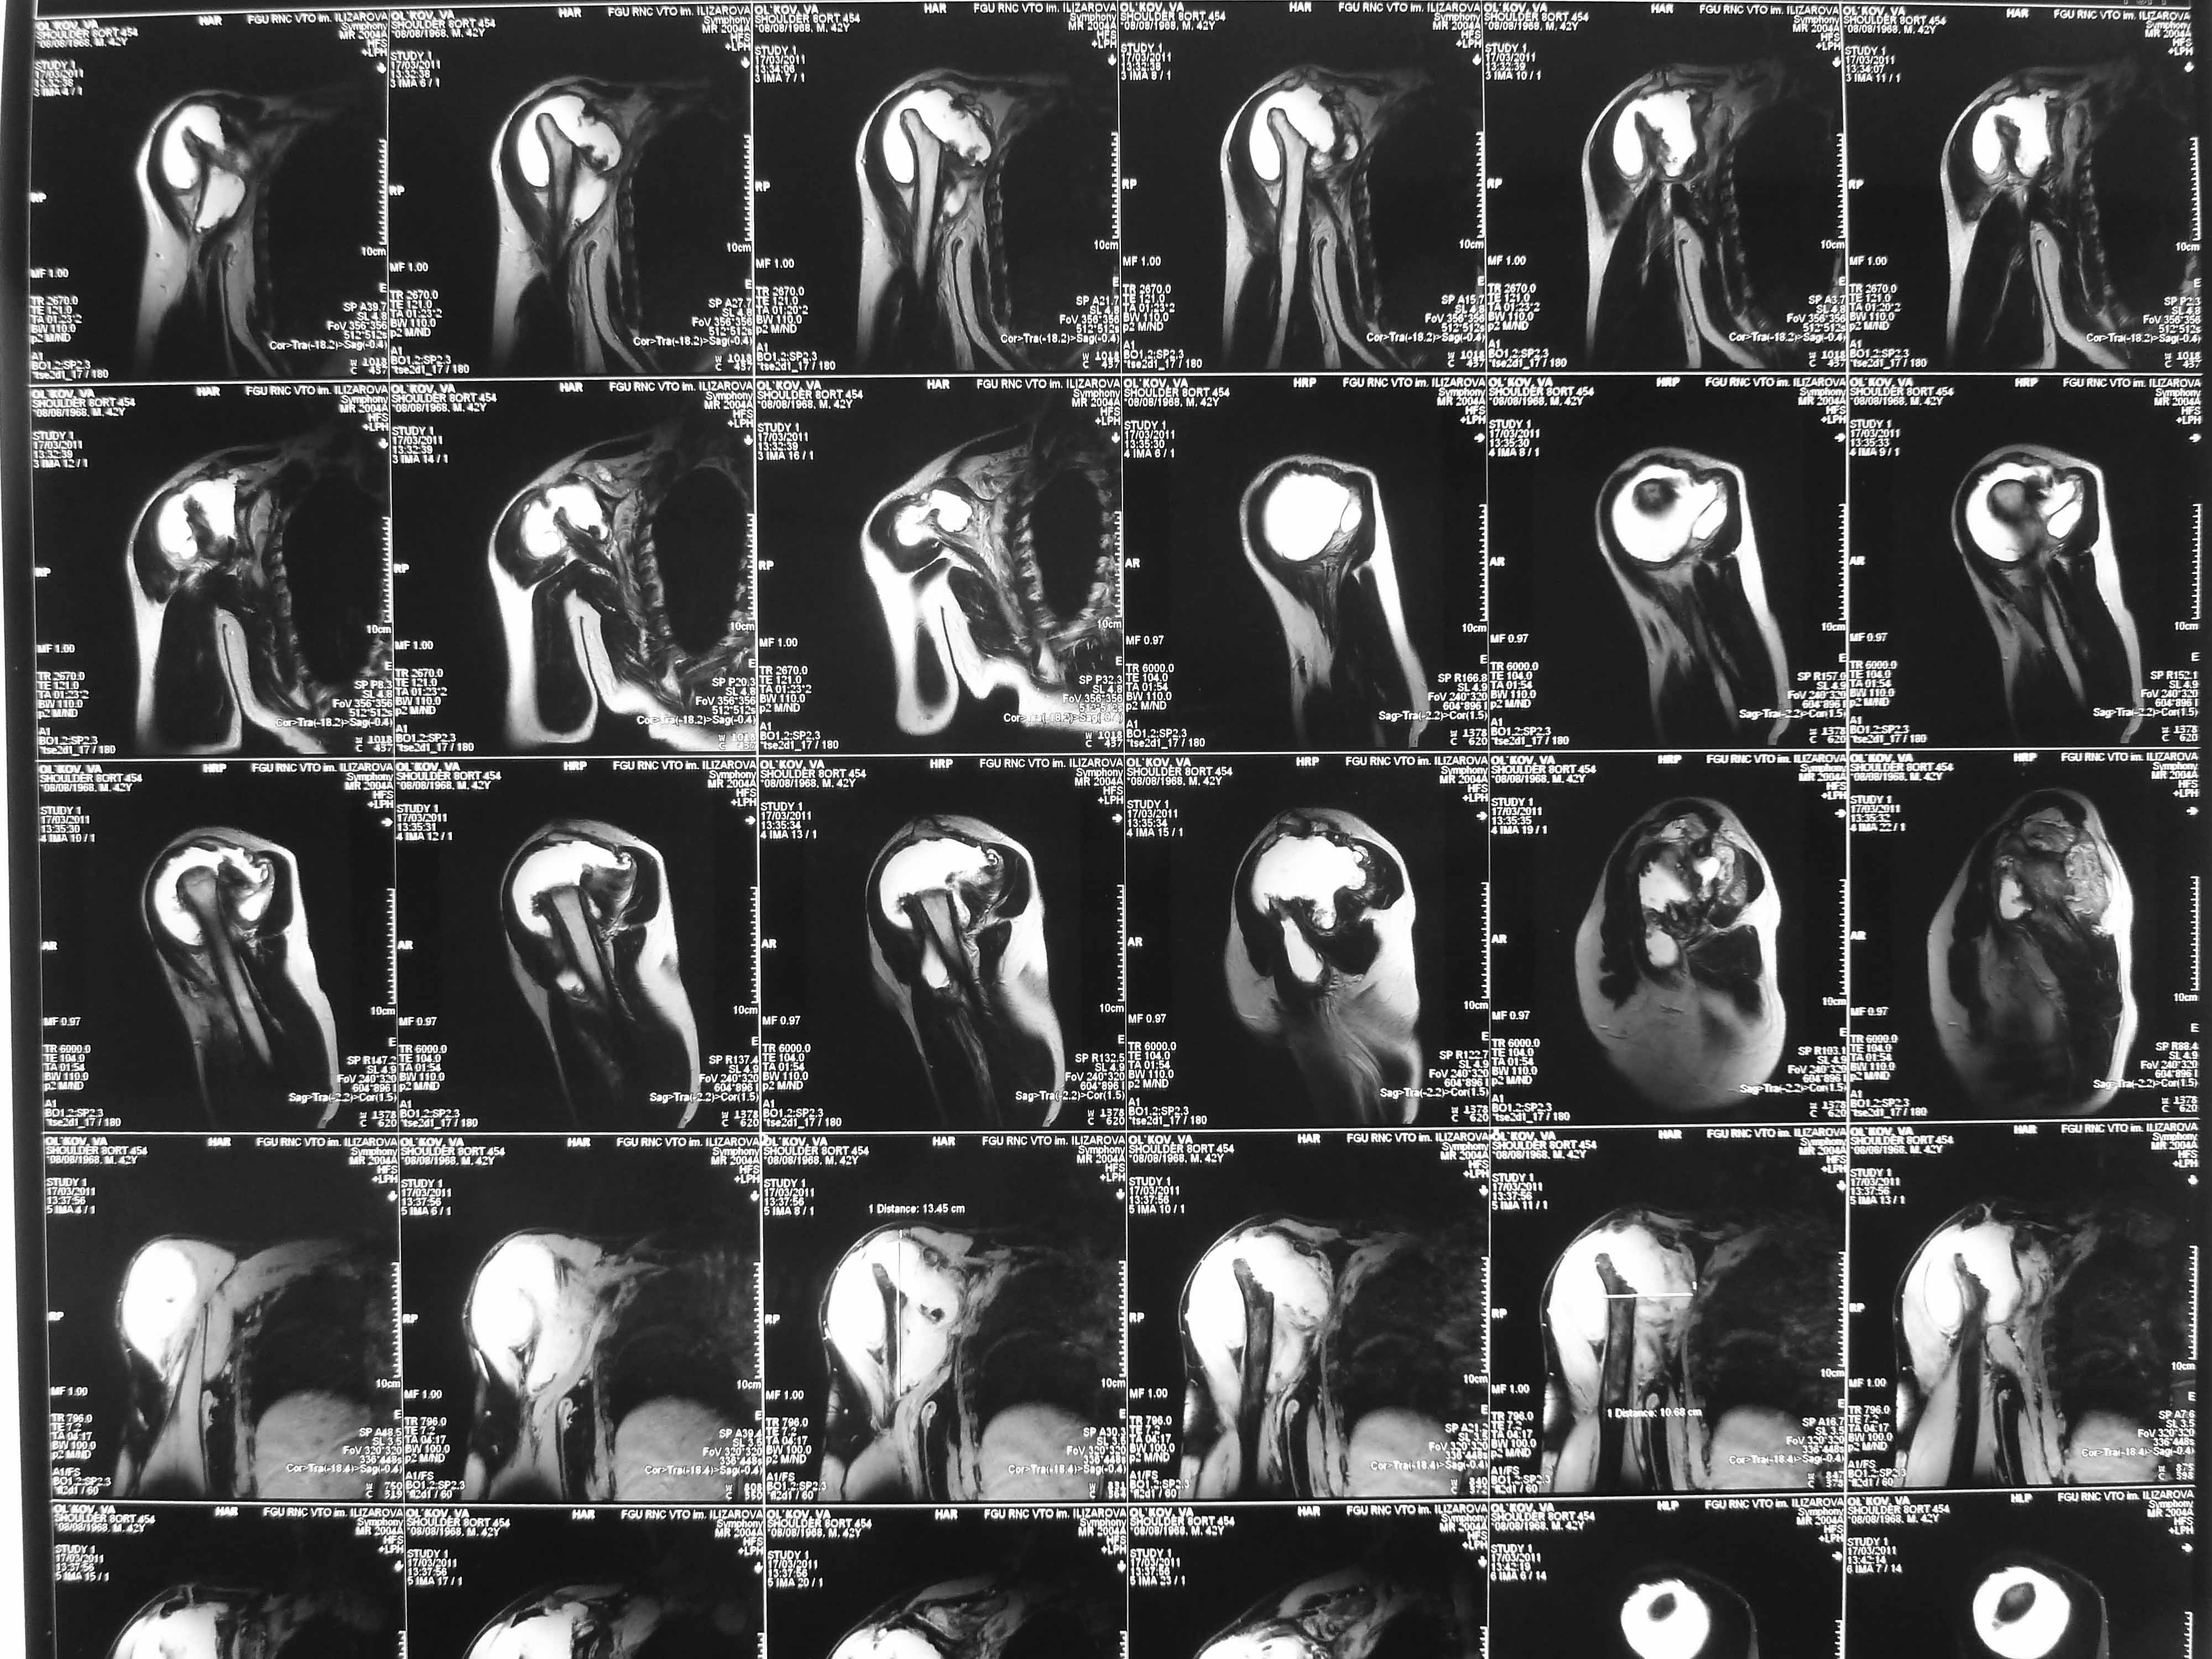

Re: Лизис костей плечевого сустава

Нужна открытая биопсия. будет саркома.

Извиняюсь, что-то фотографии сразу не прошли. сейчас исправимся.